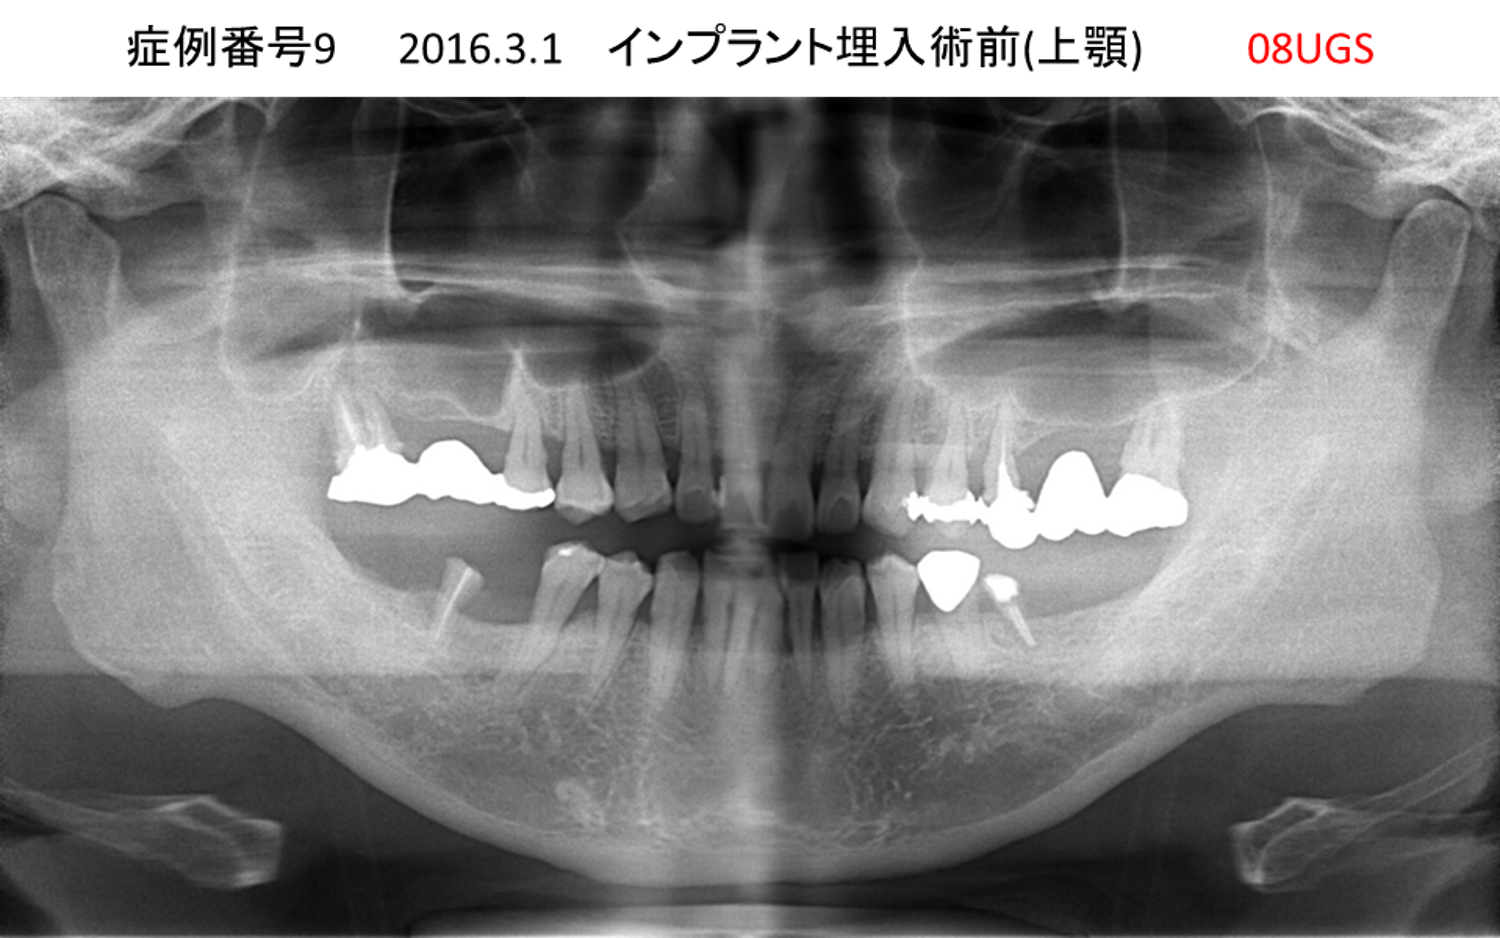

義歯が合わない、噛めない患者様のインプラント症例

| 治療名称 |

インプラントコーヌステレスコープ |

| 治療費用 |

270万円+税 |

| 治療期間 |

4か月 |

| 患者さんの症状(主訴) |

義歯が合わない、噛めない |

| 治療内容 |

インプラント、義歯作製(コーヌステレスコープ) |

| 治療結果 |

しっかり噛めるようになった。見栄えが良くなった。 |

| 治療の注意点(リスク/副作用) |

義歯が壊れた場合、インプラントが壊れた場合は再治療が必要 |